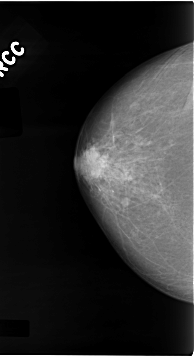

C_0074_1.RIGHT_CC

RIGHT_CC LINES 4648 PIXELS_PER_LINE 2520 BITS_PER_PIXEL 12 RESOLUTION 50 NON_OVERLAY